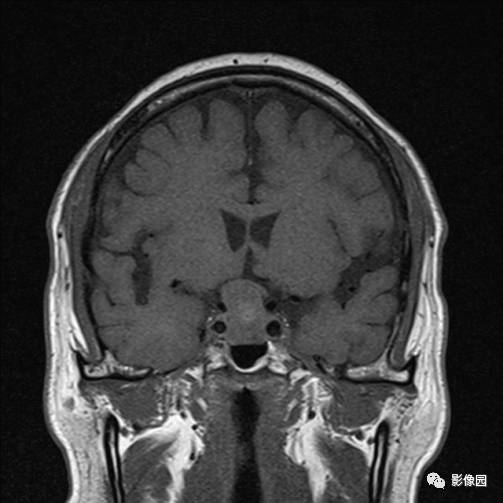

患者,女性,42岁

视力下降半月

神清语明,双侧瞳孔等大等圆,直径约3.0mm,对光反射灵敏。粗测双眼视力下降,伴双眼颞侧偏盲。四肢肌力V级,四肢肌张力正常。

独孤求败:诊断为垂体瘤,蝶鞍扩大,鞍底下陷,鞍内见突向鞍上生长的团块状异常信号,T1WI呈等及稍高信号,T2WI呈等及低信号,增强扫描病灶呈明显不均匀强化;垂体柄显示不清,视交叉受压上抬。

bnzhang07:这是典型的垂体大腺瘤,垂体大腺瘤冠状扫描显示肿瘤呈哑铃状或“束腰征”,这是由于肿瘤伸于鞍上,中部受鞍隔束缚的原因。

lovethemoon:这不是颅咽管瘤,而是垂体瘤,颅咽管瘤时可见正常的垂体结构,此患者看不到正常的垂体结构,病变内短T1短T2异常信号是出血,垂体瘤合并了出血,颅咽管瘤囊变时的信号一般是长T1长T2。

【答案】垂体瘤合并出血